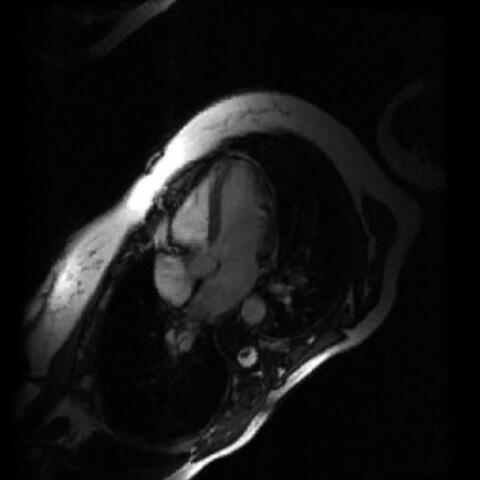

… und ein krankes Herz, das vergrößert ist. Abb.: J. Fielitz/​MDC